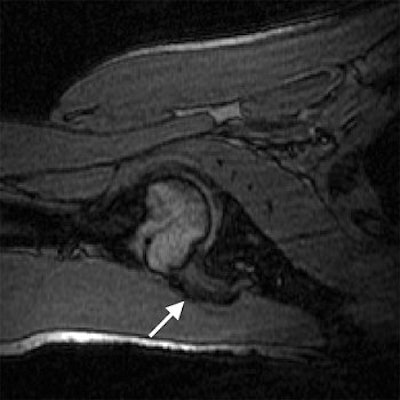

| Transverse 3D gradient-echo MR images (30/10) with volunteer in neutral position (above), unloaded ABER position at 90° external rotation (middle), and 111° external rotation (below). Note infraspinatus tendon (arrow) deformed between the greater tuberosity and posterosuperior glenoid in the loaded study. |

Based on the image evaluation, contact was observed between the supraspinatus and the posterosuperior glenoid in the unloaded and loaded ABER positions in all eight volunteers. Again, in all eight subjects, contact was noted between the infraspinatus near the insertion and posterior glenoid in the loaded and unloaded positions. Four cases were deemed grade 2. Intraobserver agreement between the two radiologists on supraspinatus and infraspinatus tendon contact with the glenoid was excellent (k = 0.875).

The researchers also assessed minimum distances and noted changes in distance in the loaded ABER position. They found that the minimum distance between the supraspinatus insertion and the acromion dipped from 16.9 mm to 5.7 mm, while the infraspinatus to glenoid distance went from 38.4 mm to 3.6 mm. The supraspinatus to glenoid distance went from 35 mm to 6.6 mm. Finally, the distance between the greater tuberosity and glenoid decreased from 21.5 mm to 3.6 mm.

This last result suggested that "a larger portion of the greater tuberosity (including the supraspinatus and infraspinatus insertions) may be important in the minimum distance measurement," the authors stated. "The infraspinatus insertion, in particular, came to within 3.6 mm from the glenoid, on average."

The group came up with a couple of recommendations based on the results. First, a decrease in minimum distance may not translate directly to clinical impingement because contact between the rotator cuff and glenoid occurs even in asymptomatic individuals during the loaded ABER position. Also, the loaded position may be more specific for internal, rather than subacromial, impingement.